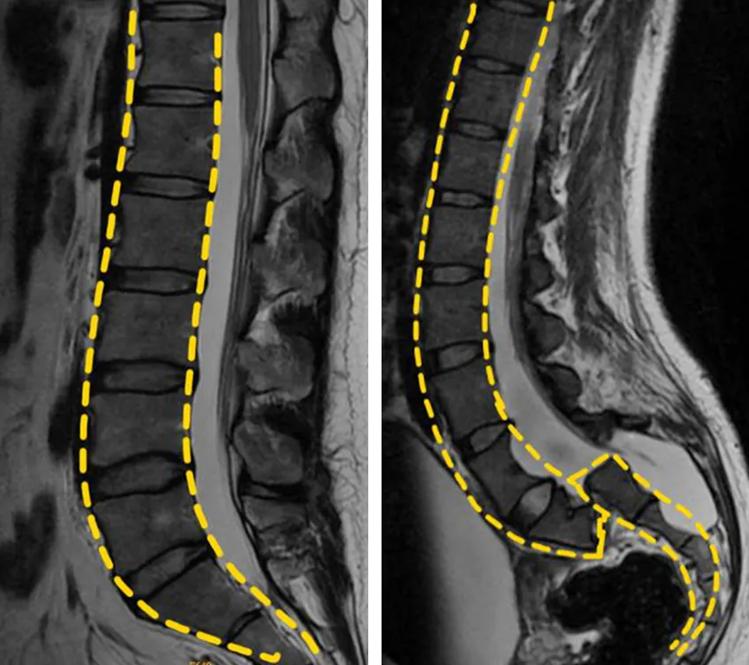

腰椎滑脱在临床中称为腰椎滑脱症,是指腰椎相邻两椎体发生了相对滑移,即某椎体相对于其临近的下位椎体产生了滑移,方向可以是向前、向后或者侧方。

腰椎滑脱为相邻两个椎体相对向前或向后发生滑移。多因为遗传性,先天性、椎弓峡部崩裂、退行性变、创伤性、病理性及医源性引起的腰腿痛,严重时可出现双侧下肢及二便功能障碍,合并椎管狭窄时可出现间歇性跛行。